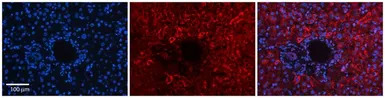

IHC-P analysis of human liver tissue using GTX46726 DNAJB12 antibody at 1:100.